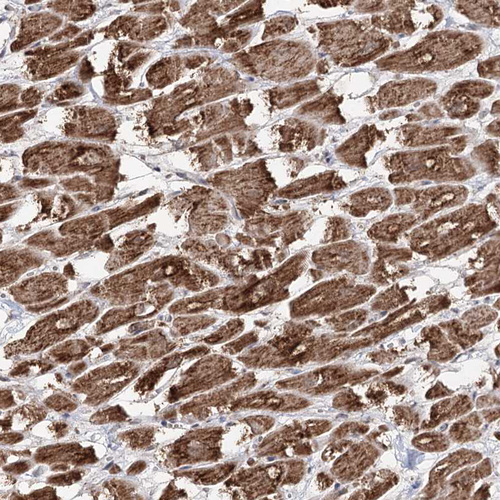

Immunohistochemistry analysis in human heart muscle and pancreas tissues using HPA038484 antibody. Corresponding PDHX RNA-seq data are presented for the same tissues.